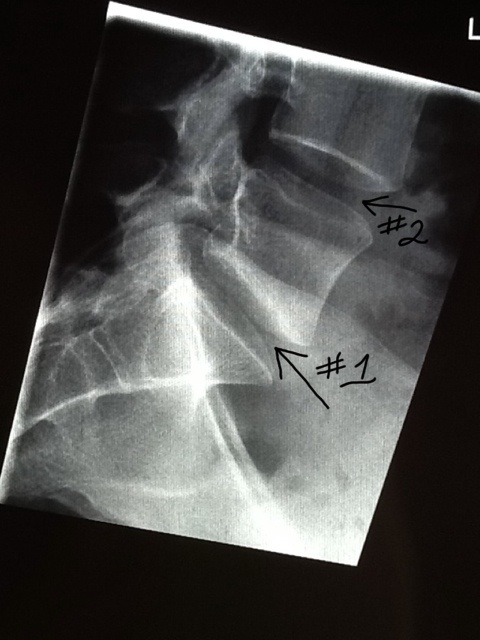

And as it turns out, not very much. I do have one disc that is dried up and cracked and so is squishing out through the crack and bulging a bit. To the right. My nerve issues are nearly all on my left side. Doc couldn’t see any reason that the bulge on the right would be pressing on a nerve on the left. So, surgery was 100% ruled out. Nothing to operate on. He did offer what I had been told were ‘shots’ but actually is an epidural. I agreed, even though I have no idea what they might be pumping into my spinal fluid, and it probably won’t help. If it does, then they know a nerve is indeed being squarshed and that’s a valuable bit of knowledge, to me. Because if the nerve isn’t being pinched at the spine, just what the hell is the issue? Cuz my leg burrrns. Or aches like it is bruised, or itches in a way that can’t be scratched.

Back to the back. Needle in 4-6 weeks, and probably another day off of work. Be interesting to see what result, if any, I get. In the meantime they said my issue appears to be muscular. My lower spine has very little curve to it. Doc said this is because the muscles are supposed to pull tight and make the curve, but mine are weak and haven’t been doing the job. I asked about any options to strengthen the muscles that might be provided by the HSE – none. So Pilates on my iPad it is then, I guess. I can’t afford classes with someone to show me how to do it right – even though I have never done regulated exercises and I doubt I do them right. Only time I ever tried anything close was the Haidong Kumdo and that is what really, really fucked my back up! Even with an instructor. Imagine what I can do to myself, by myself!